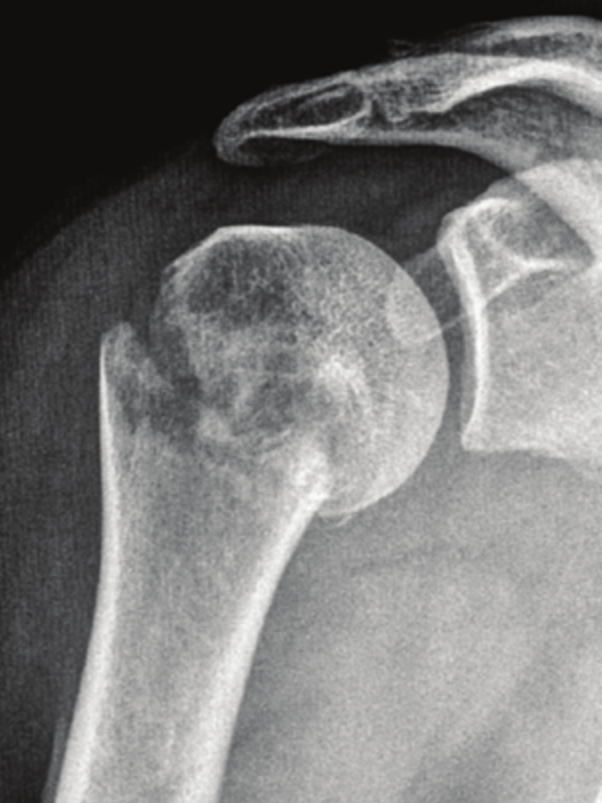

Proximal Humerus Fracture

Concentric Arthritis

Eccentric Arthritis